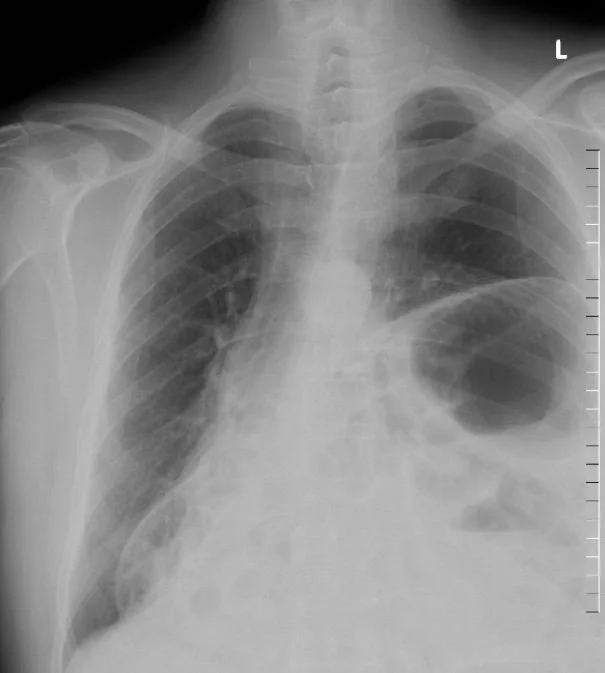

A 26 y,o woman comes to the ED with abdominal pain. Her WBC is 20K.

What could be wrong?

Our patient had a congenital Morgagni hernia.

This hernia is a defect in the foramen of the diaphragm allowing bowel to move into the chest.  The right side is affected in 90% of cases because pericardial attachments protect the  left side. In contrast, traumatic diaphragmatic hernias occur on the left side in 75-95% of case.